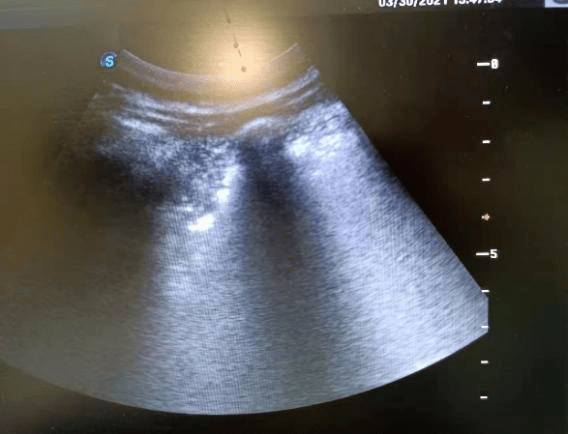

因患者病情危重 , 出科检查及进行有创操作的风险极高 , 为进一步明确诊断 , 医师与家属协商后在床旁 超声下行“超声定位引导下左肺穿刺活检术” 。

整个过程实时动态观察 , 操作流畅 , 医师配合默契 , 顺利获取组织 , 患者无不适反应 , 操作过程全程心电监测 。 活检标本送病理科 , 随访病理诊断:肺穿刺活检组织——浸润性腺癌(低分化) 。